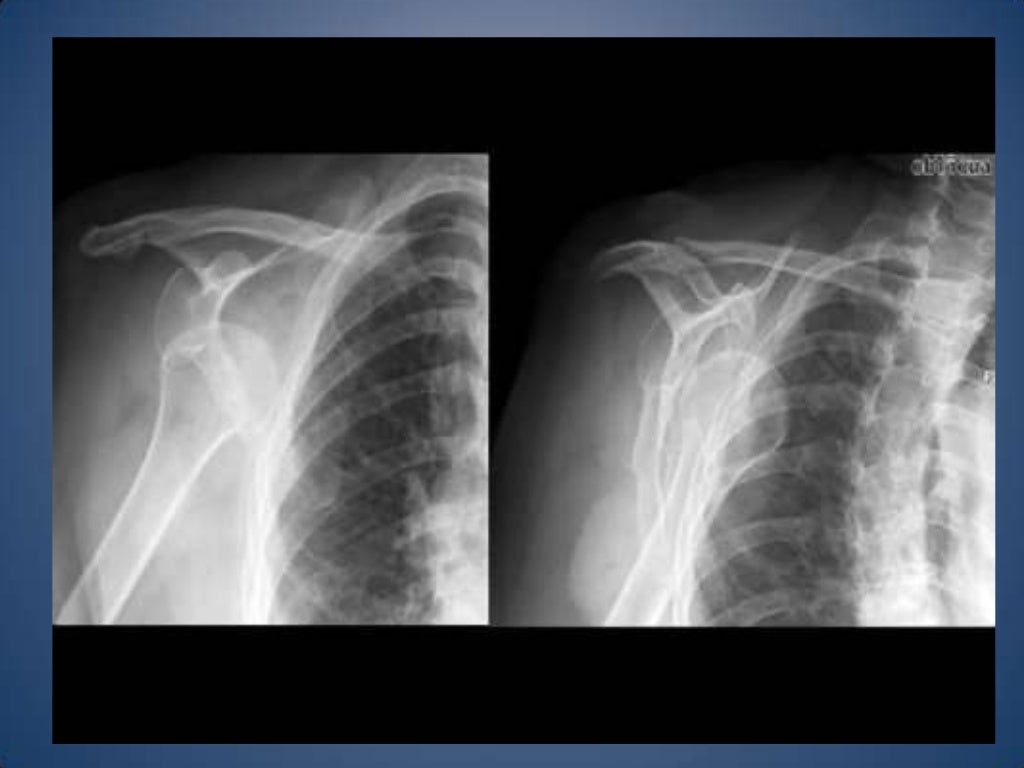

Luxación glenohumeral posterior traumática: Reporte de caso Reporte de Caso Traumatic posterior glenohumeral dislocation: A case report Isabel Silva-Ocas1,2,a, Víctor Zamora-Mostacero2,a, Juan Vargas-Ferrer2,a, Milded Silvestre-Castro2,a, Jesús Rios-Mauricio3,b, Sandro Rodriguez-Vasquez4,b 1.. Introducción. El hombro es la articulación con mayor rango de movimiento de todo el cuerpo y con mayor riesgo de luxación que cualquier otra articulación, pues se encuentra documentada en más del 45% de las luxaciones, con una incidencia de 17/100.000 al año 1,2.. Con la globalización y la aparición de nuevos deportes recreativos es posible que la inestabilidad de esta articulación se.